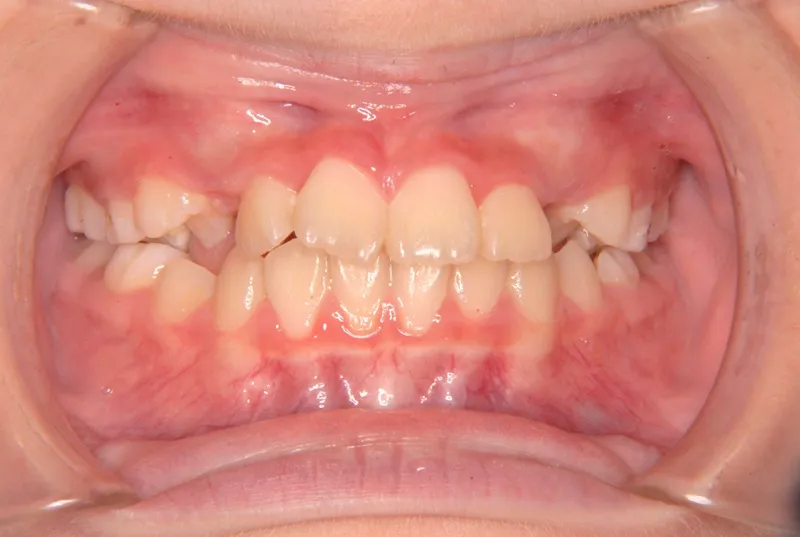

【子供の矯正(一期)】叢生・前歯がゆがんでいる・犬歯の生える隙間がない・9歳女児【M.O】

初診時年齢 小学校3年生 (女性) 主訴 前歯がゆがんでいる・犬歯の生える隙間がない

診断名 叢生 装置名

上下がガタガタで犬歯の生えるすきまがありません。

このままだと犬歯の生えるスペースがありません。放っておくと犬歯が上の位置からはえ、牙のようになってしまいます。

乳歯があるうちは上下オリジナル固定装置を利用し、永久歯が生えそろったらマルチブラケット装置を利用して治療しました。

治療回数35回、5年9ヶ月の治療期間で矯正治療を終了しました。

初診